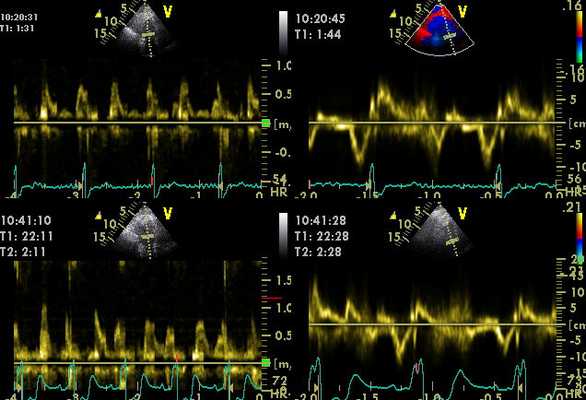

Результаты исследования изображаются в виде двухмерного графика, что дает возможность в полной мере оценить качество функционирования левого желудочка. Расшифровка результатов включает в себя оценку степени утолщения и подвижности тканей сердечной мышцы в отдельных участках.

Предварительный анализ графиков проводится специалистом сразу после их регистрации. После окончания скрининга кардиолог может просмотреть видеозапись диагностических показателей в замедленном режиме. Полученные данные сохраняются на дисках, создавая информативную базу пациента с дальнейшей оценкой динамики показателей работы сердца.

Стресс-эхокардиография — тест-исследование, в котором используется ультразвуковое изображение, чтобы выявить патологии в работе сердца и коронарных сосудов. Стресс-ЭХО-КГ используют для обнаружения снижения тока крови, нарушений сократимости зон миокарда. Во время обследования пациент занят специальным нагрузочным тестированием, а специалист следит за его давлением и сердечным ритмом. Когда пульс достигнет максимального уровня, врач с помощью УЗИ-аппарата получает изображение сердца.

Во время нагрузочного теста монитор отображает эхо в виде изображений стенок сердца и клапанов, после чего специалист будет иметь возможность распознать и диагностировать определенные нарушения в работе сердца. Любой желающий может пройти такое обследование по направлению специалистов или без него. Стресс-эхокардиография в Октябрьском (республика Башкортостан) — это эффективный способ своевременно обнаружить заболевания сердечно-сосудистой системы на раннем этапе.